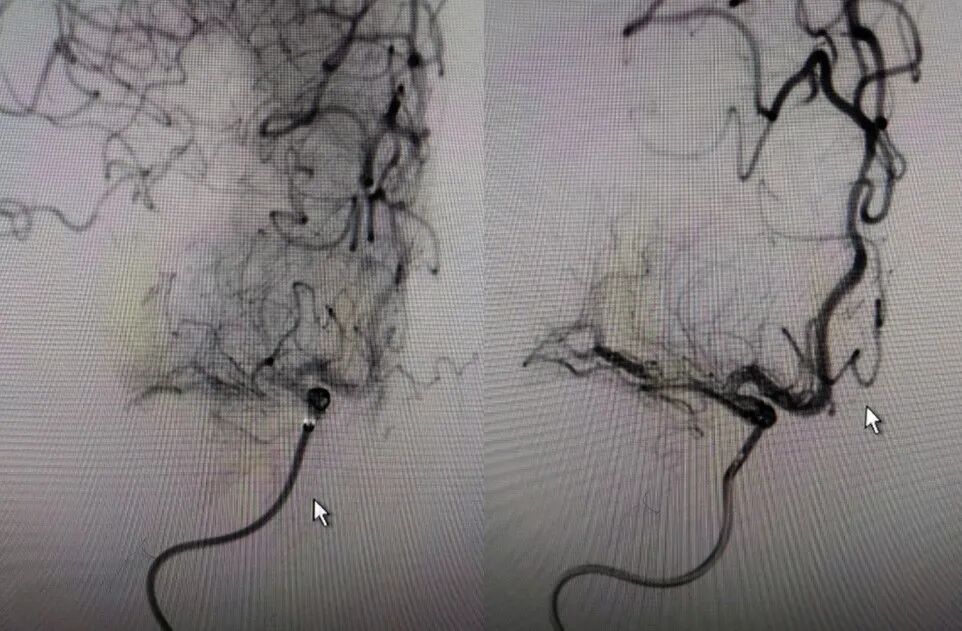

多次利用取栓支架SWIM技术对逃逸斑块进行取栓但未成功。

利用赛诺神畅 NOVA DES®内药物洗脱支架锚定后释放,血管再通,mTICI 3级,局部动脉给药替罗非班(0.2ug/kg.min)约3ml,持续15分钟。静脉(0.1ug/kg.min)持续泵入24小时后改为口服双抗。